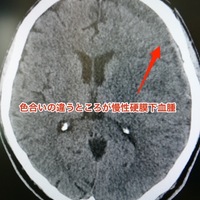

水頭症手術に対して行われるシャント手術。術後に髄液流量を調整する必要が生じた際には、バルブ圧変更を行う。シャントバルブ圧調整の実際を紹介する。